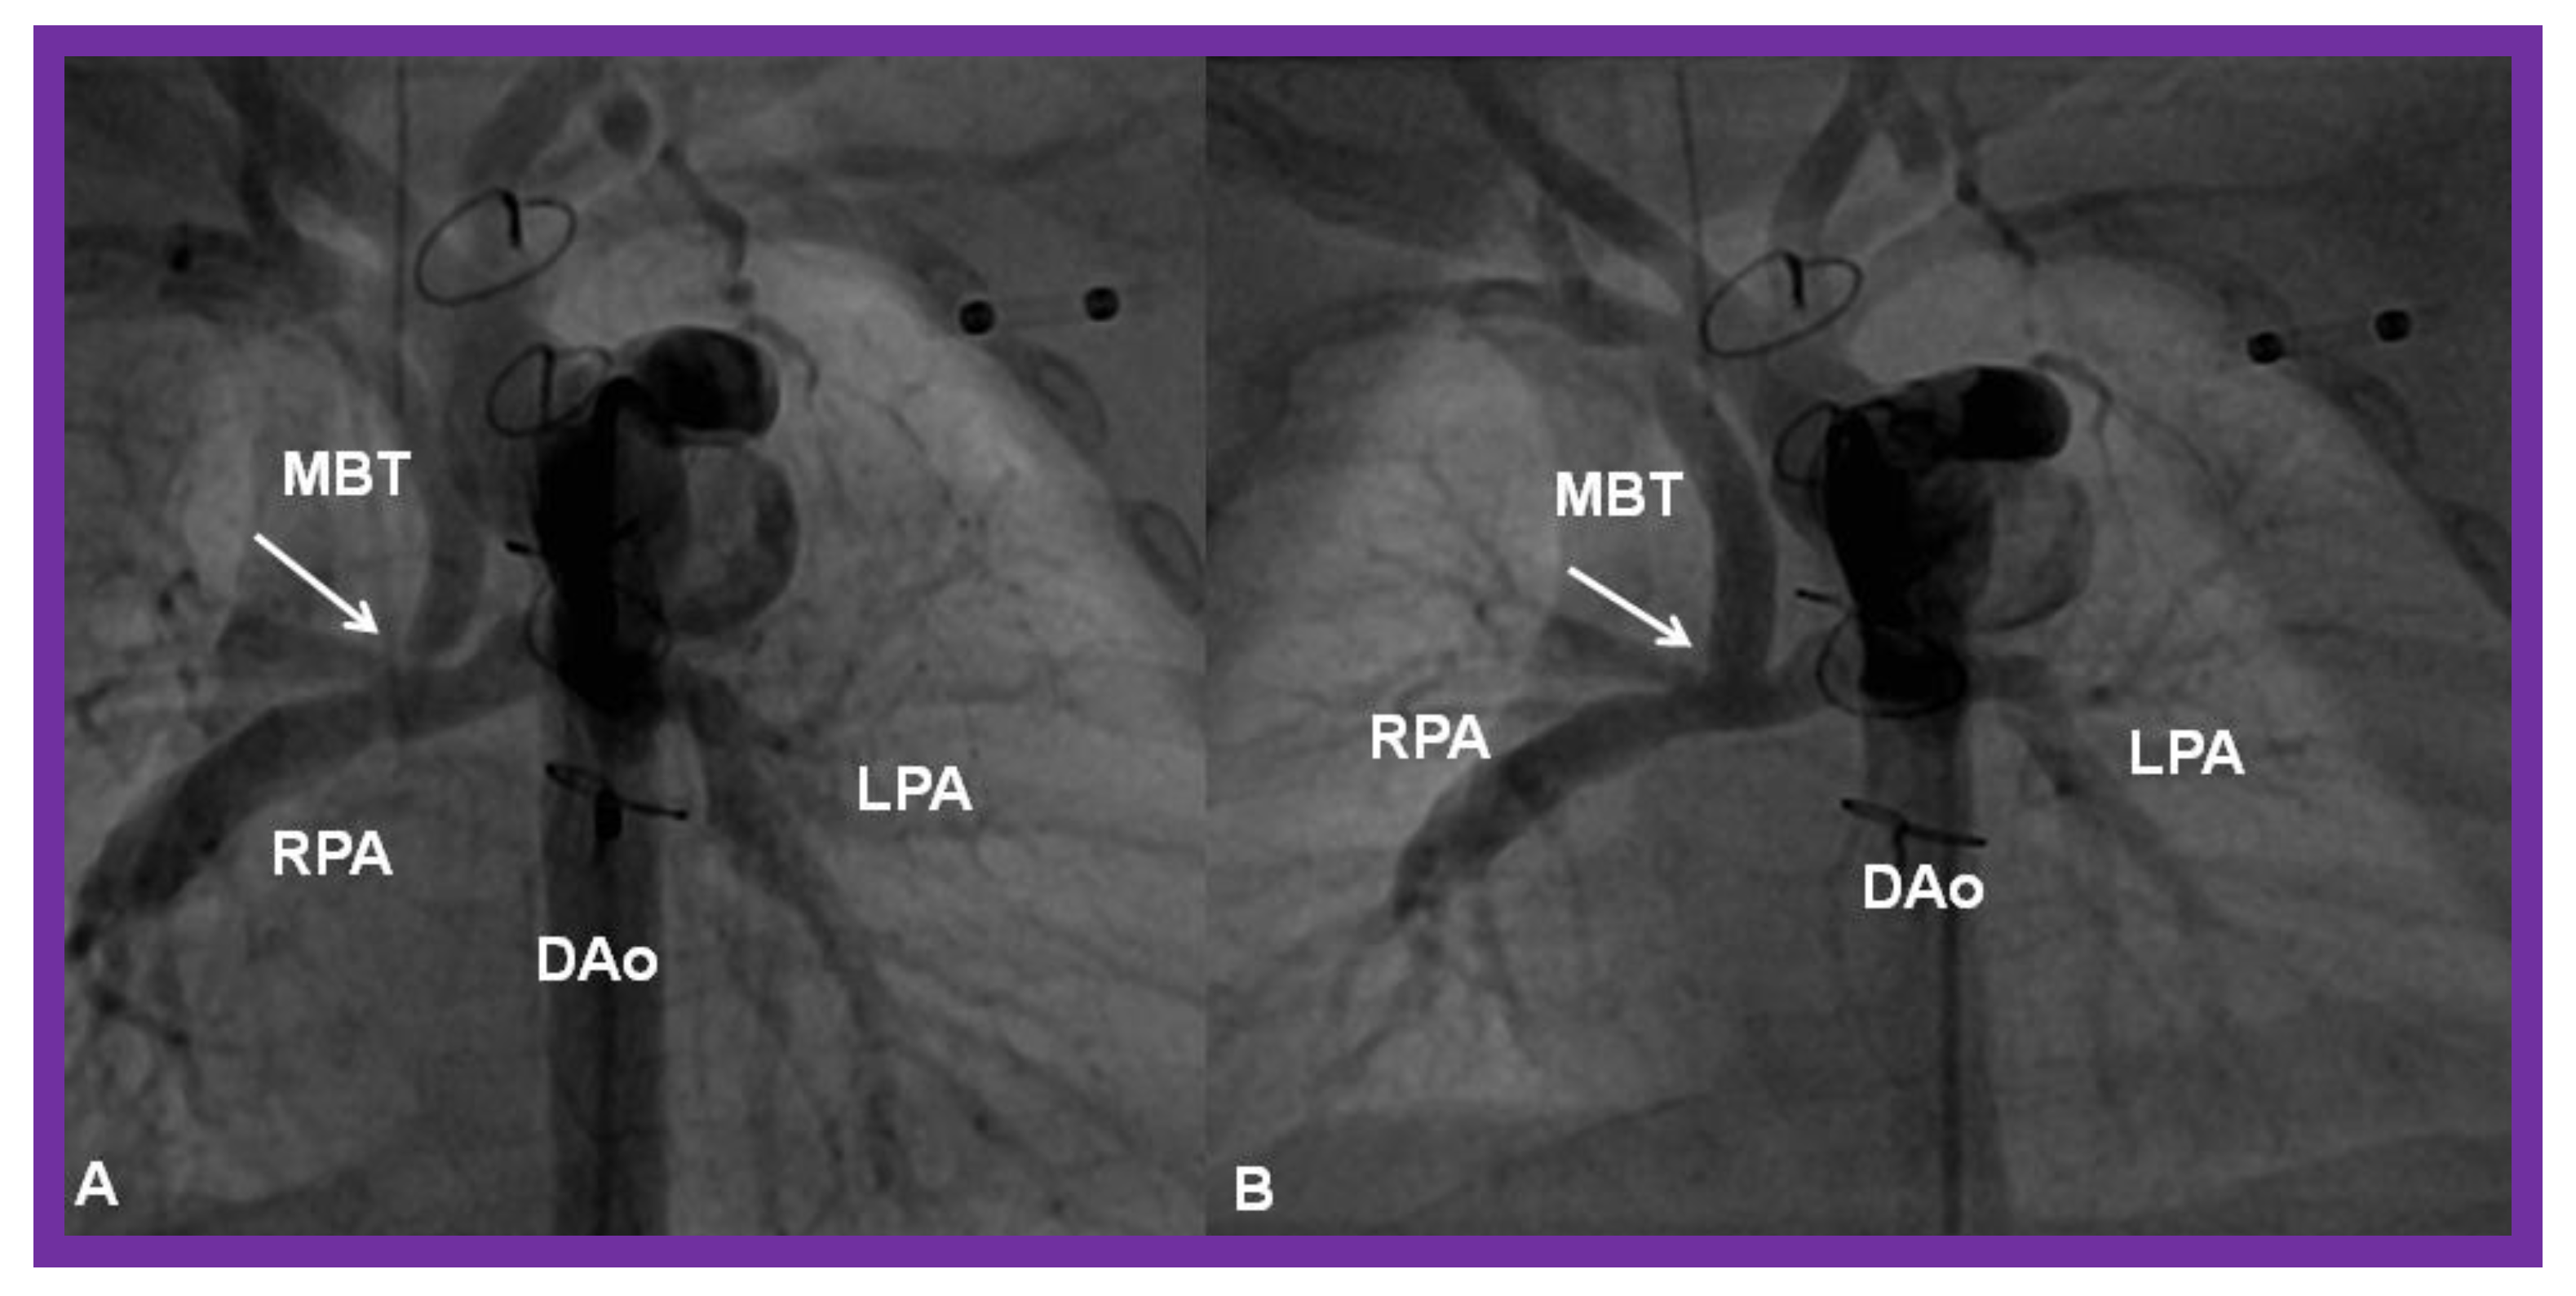

- Akintuerk, H.; Michel-Behnke, I.; Valeske, K.; Mueller, M.; Thul, J.; Bauer, J.; Hagel, K.; Kreuder, J.; Vogt, P.; Schranz, D. Stenting of the arterial duct and banding of the pulmonary arteries: Basis for combined Norwood stage I and II repair in hypoplastic left heart. Circulation 2002, 105, 1099–1103. [Google Scholar] [CrossRef] [PubMed]

- Galantowicz, M.; Cheatham, J.P. Lessons learned from the development of a new hybrid strategy for the management of hypoplastic left heart syndrome. Pediatr. Cardiol. 2005, 26, 190–199. [Google Scholar] [CrossRef] [PubMed]